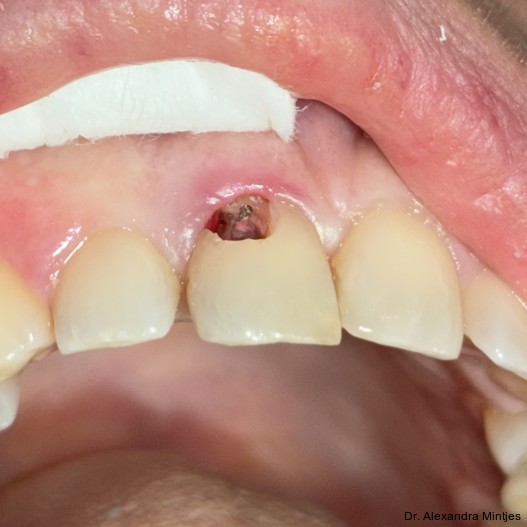

Die Behandlung erfolgte in mehreren präzisen aufeinander abgestimmten Schritten. Zunächst wurde die alte Kompositfüllung vollständig und atraumatisch entfernt, ohne eine Blutung der Schleimhaut zu provozieren. Nur durch das minimalinvasive und vorsichtige Vorgehen bei der Entfernung der insuffizienten Kompositfüllung konnte die Blutungsfreiheit erreicht und somit eine solide Grundlage für die folgenden Behandlungsschritte gewährleistet werden. Anschließend wurde die weiche Zahnhartsubstanz mithilfe eines Rosenbohrers sorgfältig exkaviert (Abb. 3). Überschüssige Guttapercha wurde ebenfalls abgetragen, um eine saubere und stabile Basis zu schaffen.

Parodontaler Befund und temporäre Versiegelung

Die Sondierung ergab eine vertikale Defektausdehnung von etwa sechs Millimetern bei einer Taschensondierungstiefe von lediglich zwei Millimetern. Dies wies somit auf eine parodontale Gesundheit hin. Der gereinigte Defekt wurde anschließend mit einem lichthärtenden Flow-Komposit versiegelt, um Unebenheiten auszugleichen und die Adaptation der geplanten CEREC-­Keramikrestauration zu optimieren (Abb. 4).